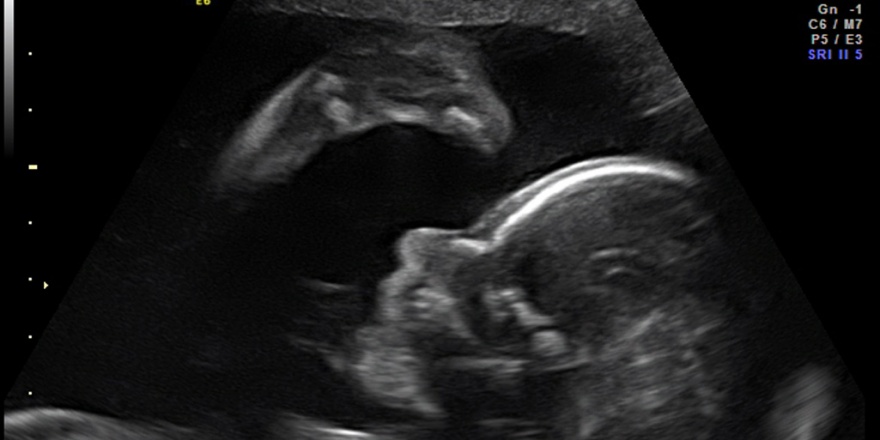

Eine Schwangerschaft gehört zu den schönsten Ereignissen im Leben einer Frau. In dieser spannenden Phase ihres Lebens wollen wir sie betreuen, begleiten und Ihnen gemeinsam mit unserer Hebamme mit Rat und Tat zur Seite stehen.

Die Schwangerschaft dauert 40 Wochen (Schwangerschaftswochen, oft als Kurzform SSW), gerechnet nach dem ersten Tag der letzten Regelblutung. In dieser Zeit führen wir regelmäßige Untersuchungen durch.